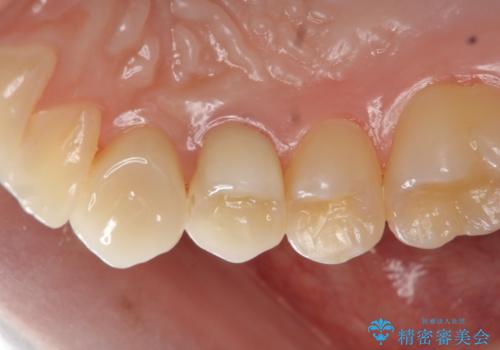

虫歯で歯が折れた セラミック審美修復

- 食事中に急に歯が折れ、周囲の歯も痛みだし治療を希望され来院されました。

ジルコニアクラウンによる咬合機能回復、根管治療を行い歯の痛みをとり長期的な予後の見込める治療を計画します。

- 26万円(仮歯・ファイバーコア・ジルコニアクラウン×2)費用は治療当時の料金となります